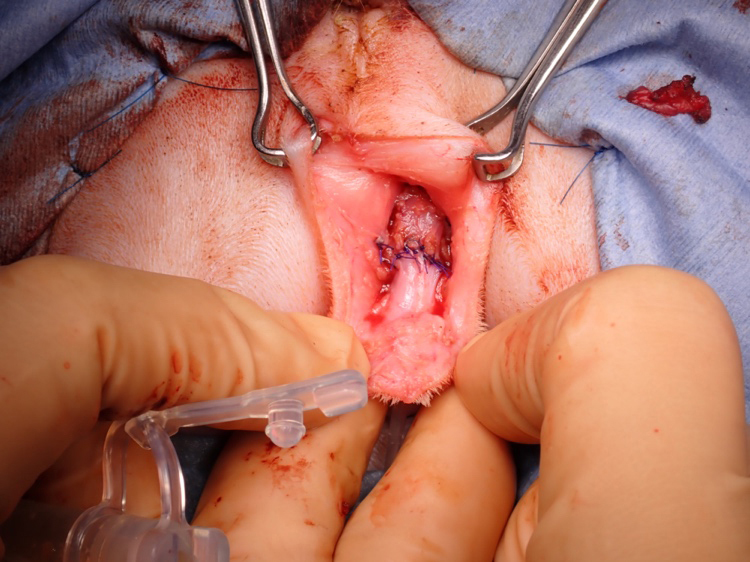

包皮の粘膜部分を筒状に形成

術創